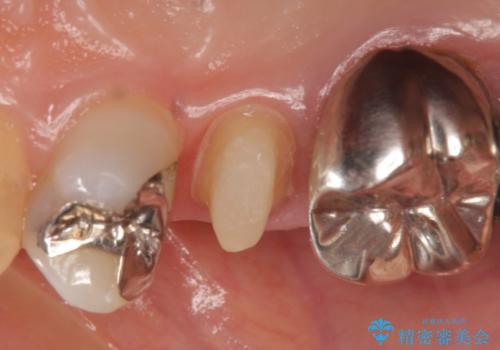

- 右上5番目の歯がなにもしなくてもズキズキ痛むので診て欲しいといらっしゃった方の症例です。

診査の結果神経を保存するのは困難だったため、根管治療を行った後、オールセラミッククラウンによる補綴を行いました。